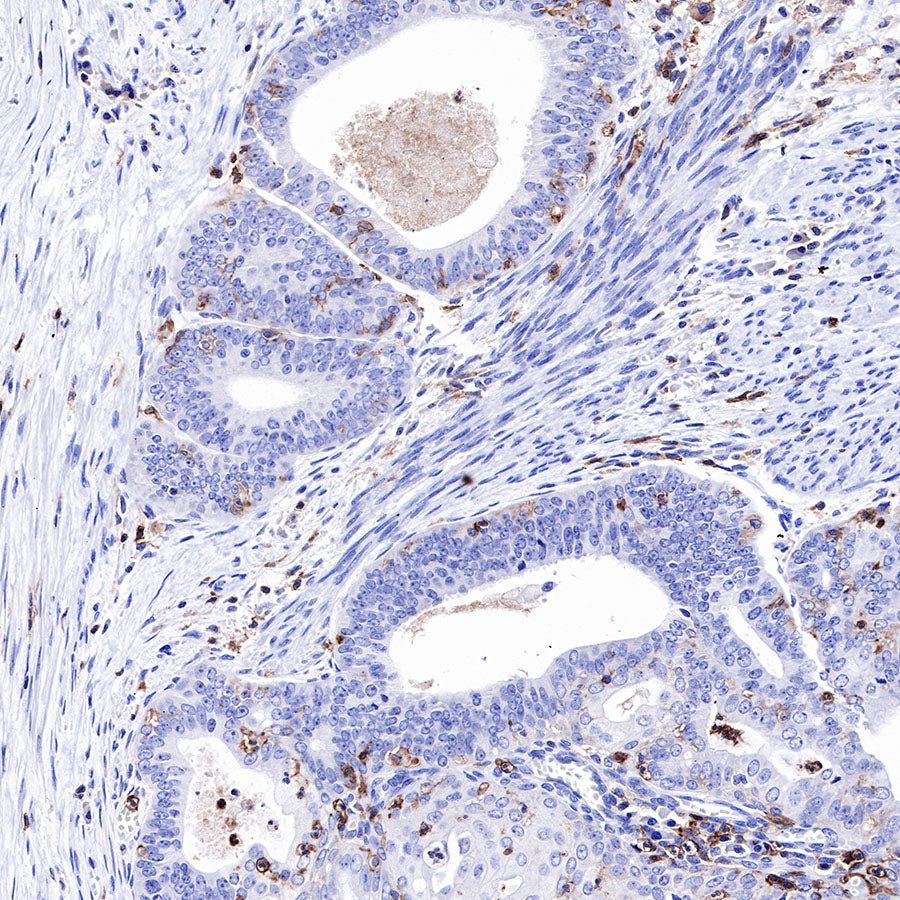

IHC shows positive staining in paraffin-embedded human colon. Anti-CD43 antibody was used at 1/1000 dilution, followed by a HRP Polymer for Mouse & Rabbit IgG (ready to use). Counterstained with hematoxylin. Heat mediated antigen retrieval with Tris/EDTA buffer pH9.0 was performed before commencing with IHC staining protocol.

IHC shows positive staining in paraffin-embedded human liver. Anti-CD43 antibody was used at 1/1000 dilution, followed by a HRP Polymer for Mouse & Rabbit IgG (ready to use). Counterstained with hematoxylin. Heat mediated antigen retrieval with Tris/EDTA buffer pH9.0 was performed before commencing with IHC staining protocol.